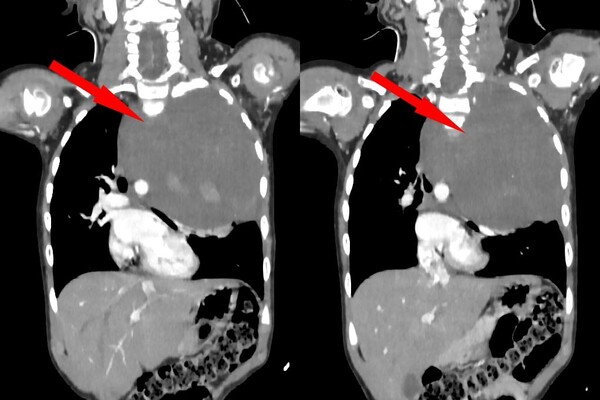

Родители показали дочь врачам, когда заметили у нее небольшую припухлость в области шеи. Специалисты по месту жительства выявили огромное новообразование размером со страусиное яйцо, которое сдавливало сердце и легкое. Сквозь ткань опухоли проходили крупные сосуды: «позвоночная артерия, питающая головной мозг, и подключичная артерия с ее ветвями, питающая левую руку». После телемедицинской консультации ребенка направили в Москву.

«Учитывая гигантский размер опухоли и ее расположение вблизи множества жизненно важных структур, мы использовали расширенный доступ по типу «раковины моллюска». Он предполагает рассечение не только межреберного промежутка, но и самой грудины, что позволяет «раскрыть» грудную клетку, как раковину», — рассказал заведующий отделением реконструктивной и восстановительной хирургии грудной полости РДКБ, к.м.н. Евгений Андреев об операции.